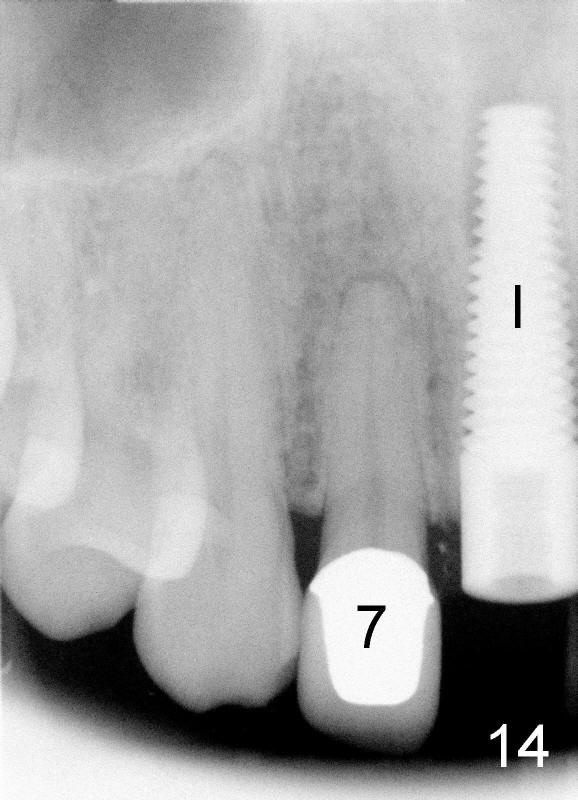

当我们拔出3.5毫米钻头(图五:最后一个钻头)时,就可以看见在舌侧骨板植牙洞型制备(图十一:圆圈)。图十二,图十三分别显示立刻植牙正面观和切缘观,植牙几乎占据所有牙槽窝空间,不需植骨或者缝线。植牙好像没有侵犯邻牙牙根(图十四,图十五,包括七号牙:侧切牙),其实只要熟悉局部解剖(图六至图十),即刻植牙反而容易进行。图十五虚线代表切牙孔,挺接近植牙(I),术后渗血较多,可能与此有关。除此之外,术后病人恢复很快。